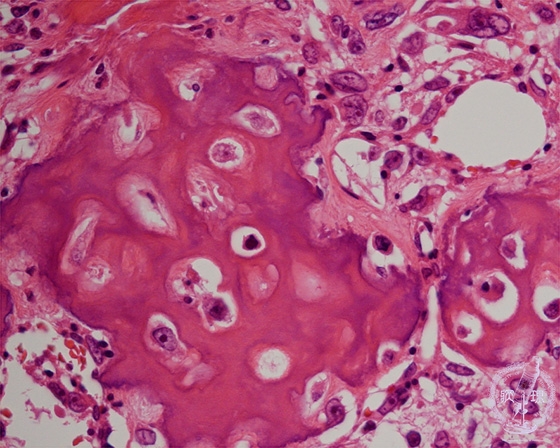

- ★(6)Osteosarcoma

Microscopic view (HE; high power view): Tumor is composed of osteoid with tumor cells with hyperplastic nuclei (within the frame).